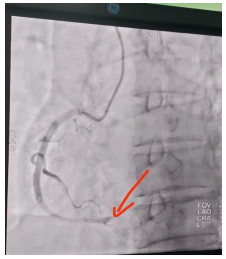

14时12分,患者通过急诊专用通道被直接送入介入导管室。14:20进行穿刺。14时34分,导丝顺利通过右冠远端闭塞病变处,行PTCA及冠脉内血栓抽吸及冠脉内溶栓开通血管,复查造影显示,远端血流恢复至正常水平(TIMI 2+级)。